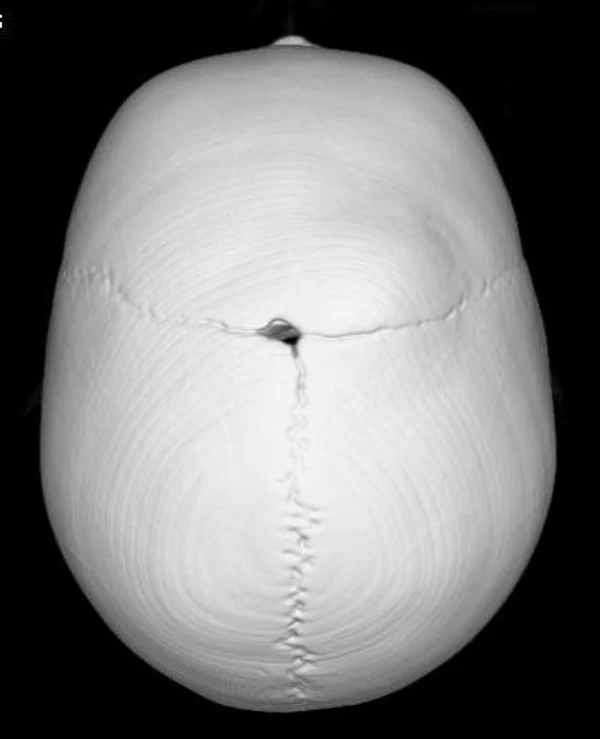

Удаление опухолей черепаВ качестве примера лечения пациентов с опухолями черепа привожу личное наблюдение пациента грудного возраста с опухолью черепа. В возрасте 1 мес. у ребёнка в затылочной области слева родителями обнаружено плотное образование диаметром 5 мм. За 3 мес. до госпитализации образование значительно увеличилось в размерах. При поступлении в возрасте 6 мес. в затылочной области слева (в проекции лямбдовидного шва) имеется безболезненное, плотное, неподвижное, бугристое образование размерами 5 х 4 х 2 см. При КТ и МРТ головы выявлена опухоль черепа в области астериона слева, обладающая преимущественно интракраниальным ростом (рис. 30 а). Ребёнку выполнено удаление опухоли черепа (рис. 30 б). Образовавшийся дефект черепа больших размеров закрыт перфорированной титановой пластиной (рис. 30 в). При наблюдении пациента в течении 2-х лет рецидива заболевания и деформации черепа не отмечалось.